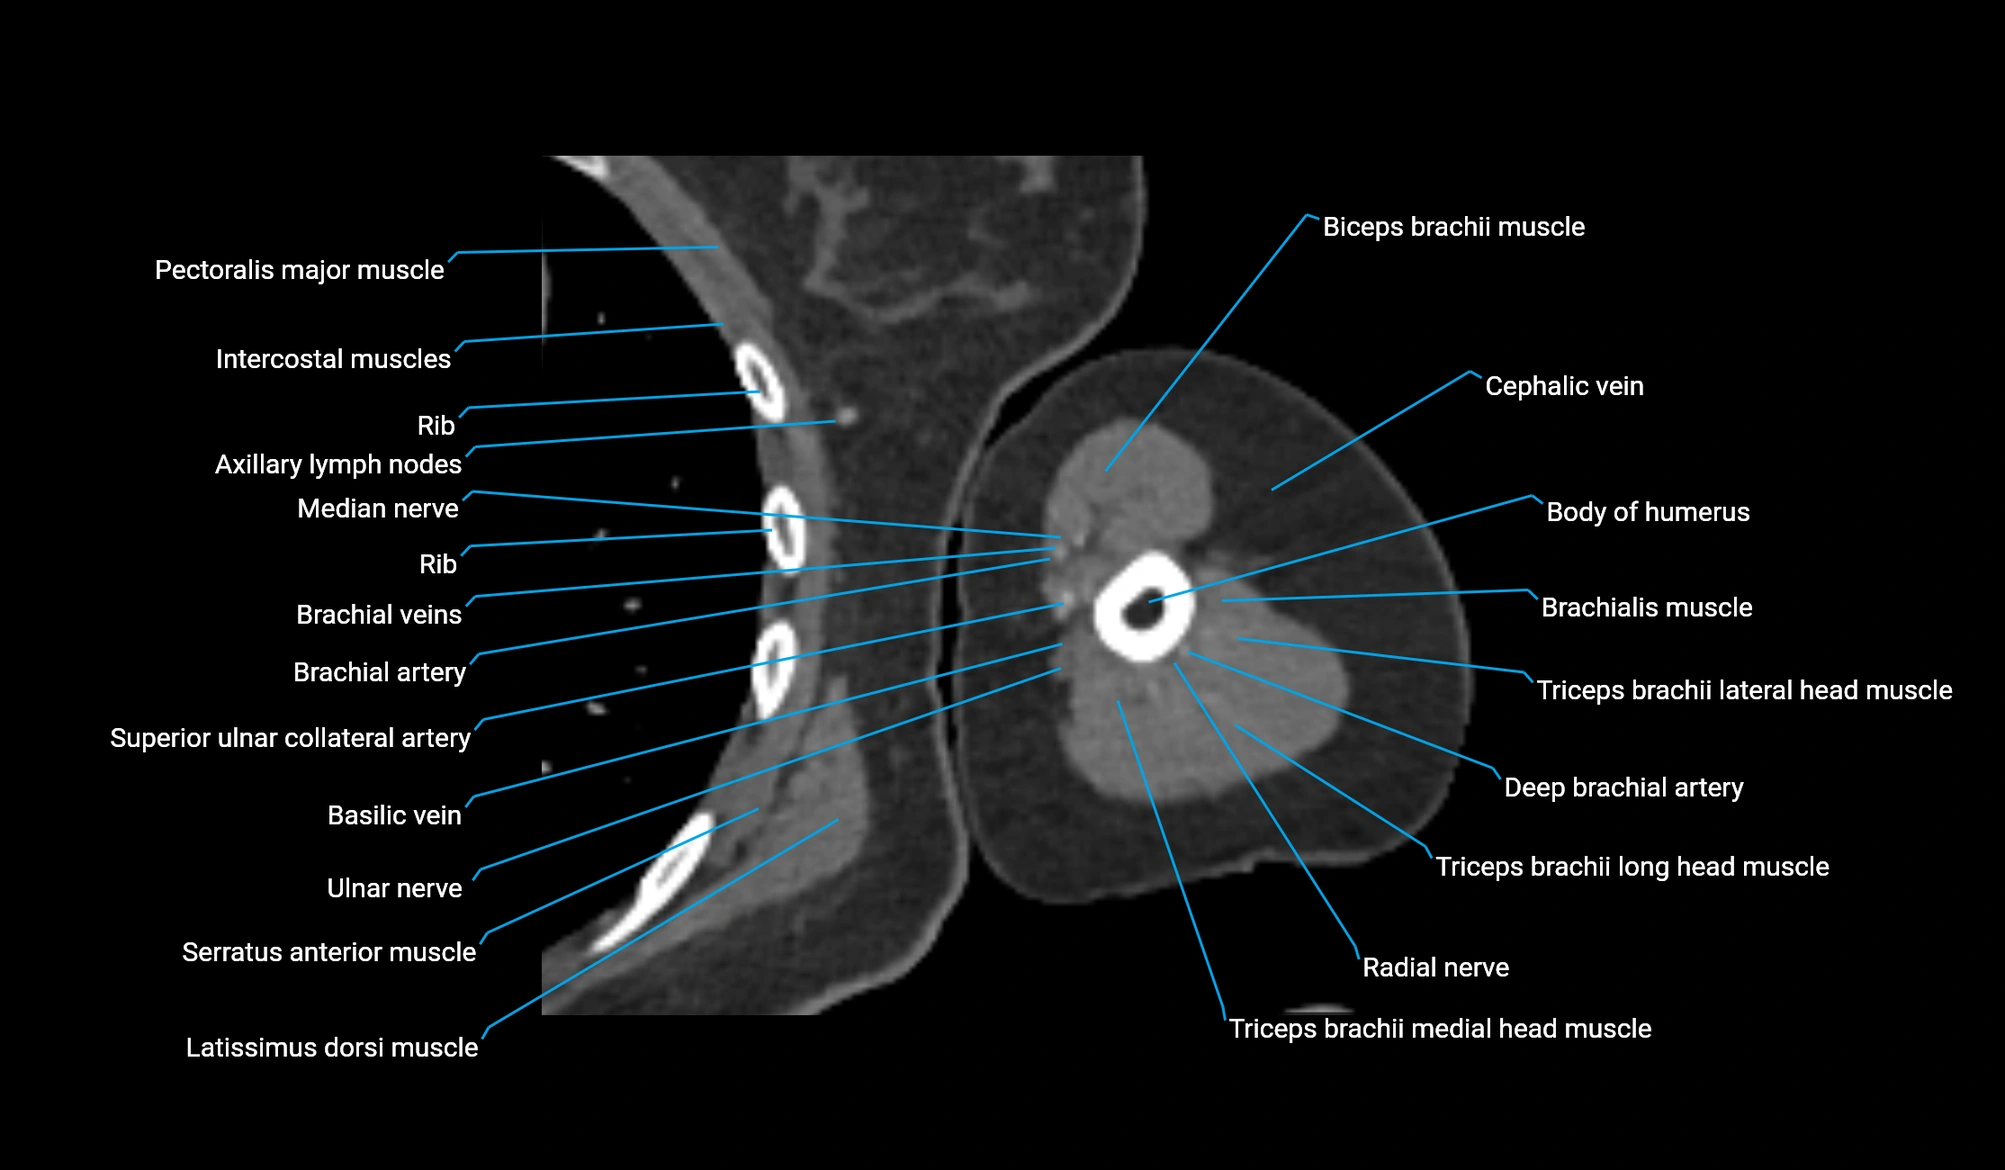

CT image